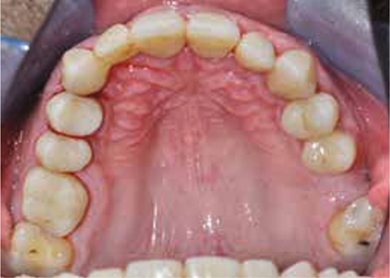

Afb. 3

Occlusaal aanzicht van de bovenkaak.

Bij het extraoraal onderzoek zie ik een lichte hypertrofie van de m. masseter. Intraoraal tref ik een ernstig versleten dentitie aan waarbij de slijtage niet passend bij de leeftijd kan worden genoemd (afbeelding 2-7 en tabel 1) .